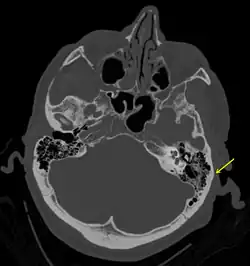

A subtle temporal bone fracture as seen on a CT scan

Temporal bone fractures

Acute injury to the internal carotid artery (carotid dissection, occlusion, pseudoaneurysm formation) may be asymptomatic or result in life-threatening bleeding. They are almost exclusively observed when the carotid canal is fractured, although only a minority of carotid canal fractures result in vascular injury. Involvement of the petrous segment of the carotid canal is associated with a relatively high incidence of carotid injury.[10]